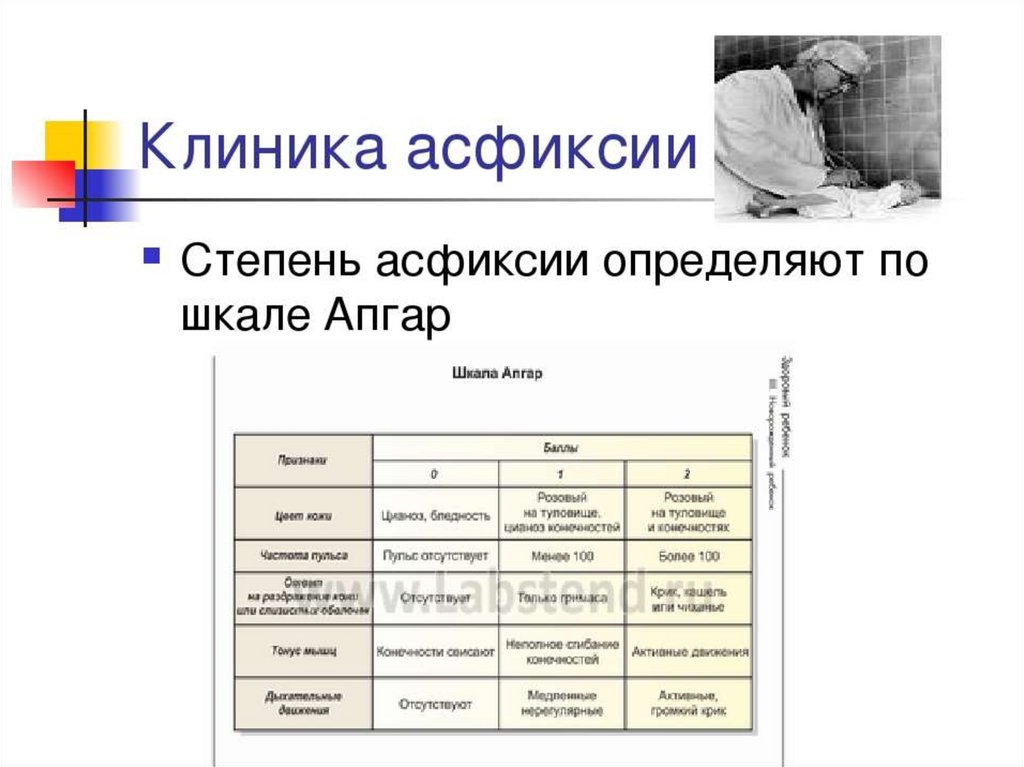

Шкала Апгар: что считать нормой для новорожденных